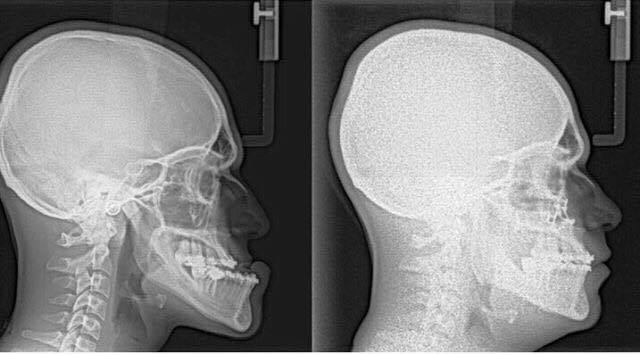

Any of these symptoms can exist at birth, be acquired after birth as a result of hereditary or environmental influences, or as a result of trauma to the face. Before any treatment begins, a consultation will be held to perform a complete examination with x-rays. During the pre-treatment consultation process, feel free to ask any questions that you have regarding your treatment. When you are fully informed about the aspects of your care, you and your dental team can make the decision to proceed with treatment together.

Dr.Al-jandan uses modern computer techniques and three-dimensional models to show you exactly how your surgery will be approached. Using comprehensive facial x-rays and computer video imaging, we can show you how your bite will be improved and even give you an idea of how you'll look after surgery. This helps you understand the surgical process and the extent of the treatment prescribed. Our goal is to help you understand the benefits of orthognathic surgery.